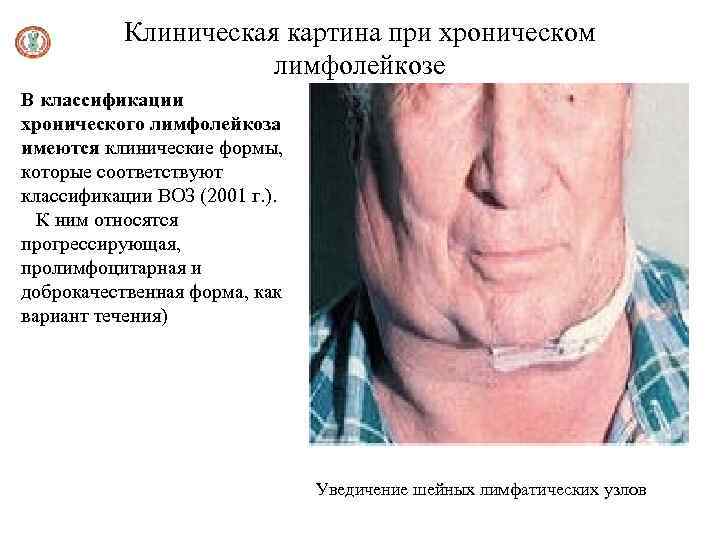

Клиническая картина при хроническом лимфолейкозе В классификации хронического лимфолейкоза имеются клинические формы, которые соответствуют классификации ВОЗ (2001 г. ). К ним относятся прогрессирующая, пролимфоцитарная и доброкачественная форма, как вариант течения) Уведичение шейных лимфатических узлов